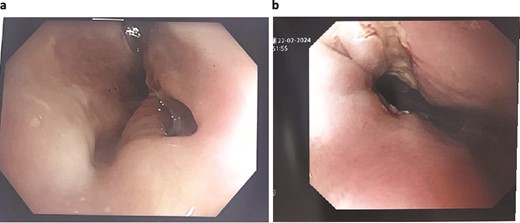

On day 2 post-diagnosis, the patient underwent an OGD, VACStent insertion, and ultrasound-guided pleural drain placement. The endoscopy revealed a 2 cm linear defect in the lower oesophagus just above the gastroesophageal junction (Fig. 3), and the VACStent was connected to 125 mmHg of negative pressure, confirming appropriate positioning. The patient tolerated the procedure well without intraoperative complications and was transferred to the ICU intubated.

Patient Three: Before VACStent insertion, showing the oesophageal defect.